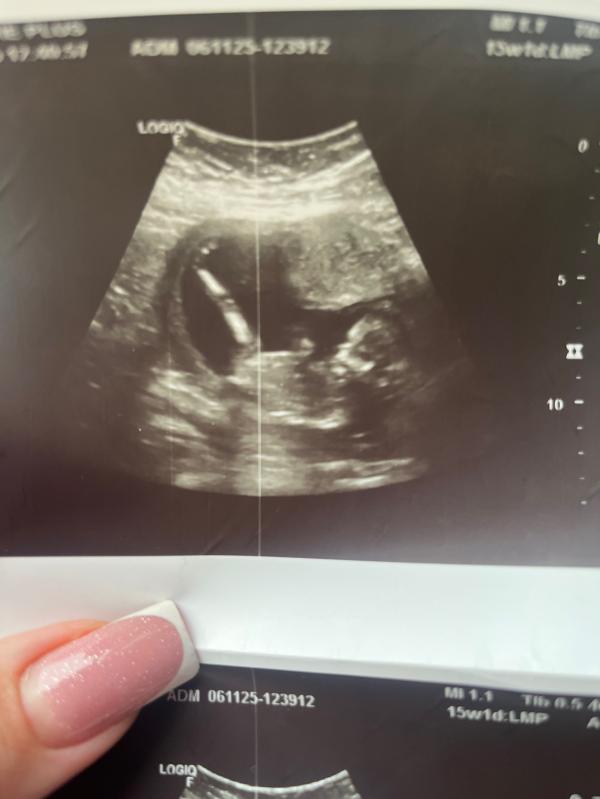

Ожидание второй дочки: радость и счастье мамы

post image

Мы ждем вторую девочку💕

Как же я счастлива❤️